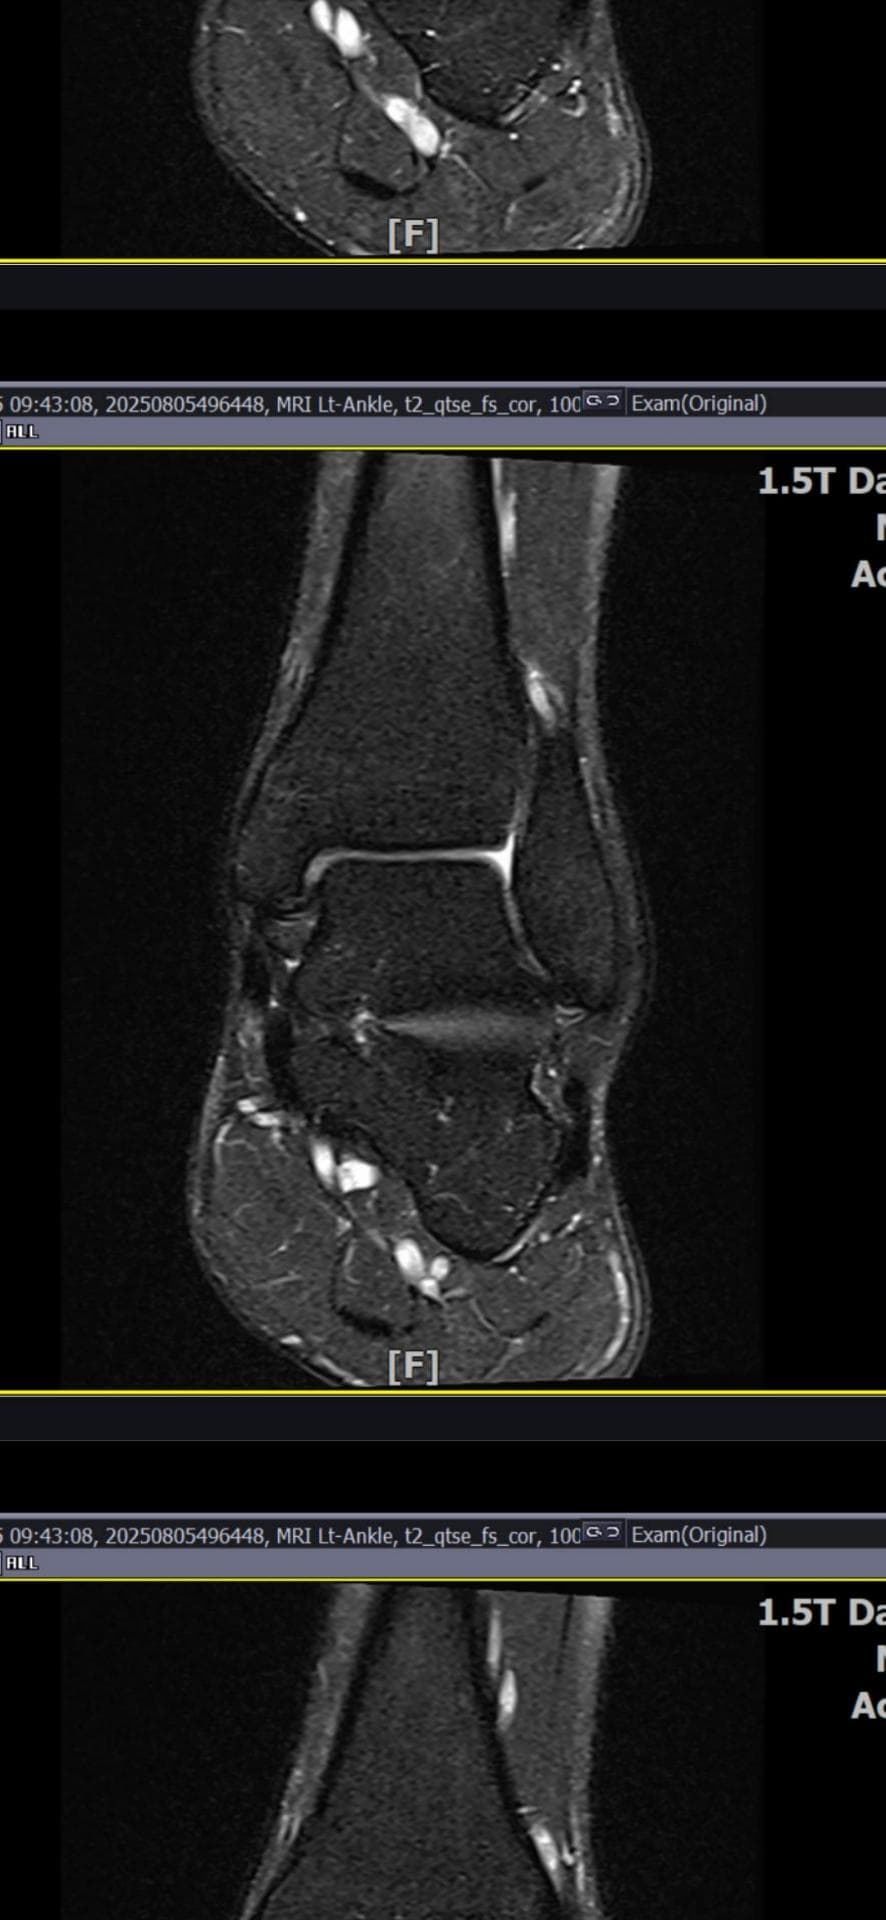

그래도 통증이 남아 8월 5일에 MRI를 촬영했는데, 병원에서는 “인대는 이어져 있고, 이 정도면 재활운동으로 호전될 것”이라는 설명을 들었습니다.

올려주신 mri를 보면 전거비인대는 연속성이 유지되고 있고 파열이나 큰 손상 흔적은 없어 재활로 회복 가능한 상태로 보입니다 다만 3개월 가까이 활동 시 통증과 미열감이 남아 있는 것은 조직 회복이 아직 완전히 끝나지 않았거나 주변 연부조직 관절 움직임 제한 등으로 인한 과민 반응일 수 있습니다.

초음파와 비교하면 mri 상으로 인대 연속성이 확인되므로 심각한 악화나 재파열은 아닌 것으로 판단됩니다

MRI상에서는 인대의 회복이 이루어지고 있는 덧으로 보이지만 인대의 회복은 소요되는 시간이 오래 걸리고, 주변 근육의 약화나 기능 저하로 인해 통증이나 불편감이 지속될 수 있습니다.